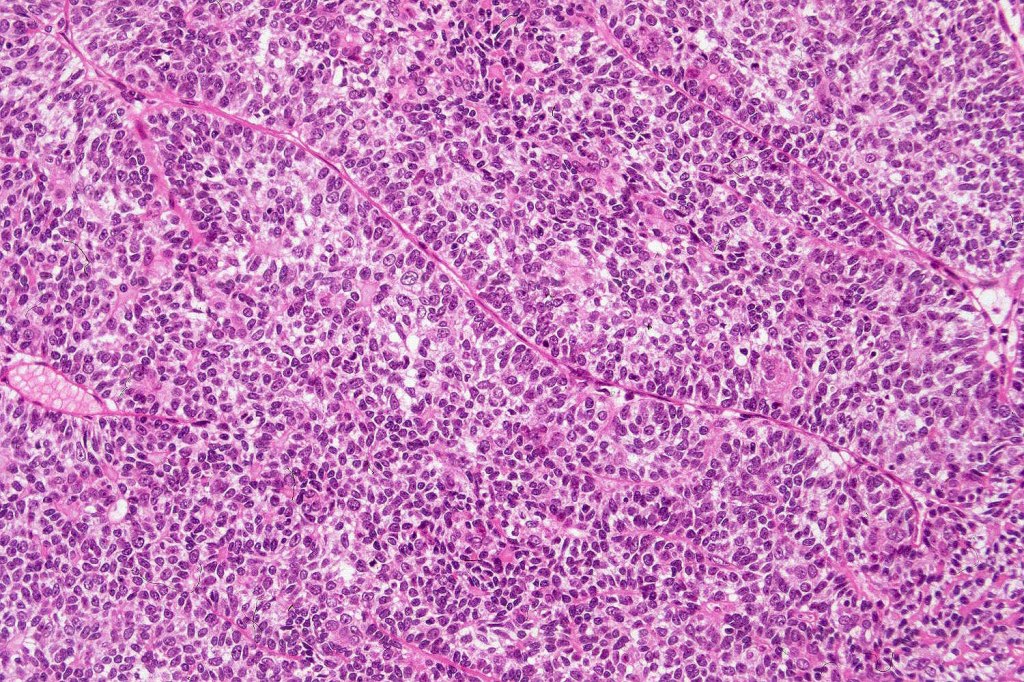

Histological features

•Pre-existent spiradenoma

•Malignant component shows loss of dual cell population, increased mitotic activity, atypical mitoses & necrosis

•1. Salivary gland type basal cell adenocarcinoma-like pattern, low grade (BCAC-LG)

•The alternative classification into low grade (with only mild atypia and increased mitotic activity) and high grade variants has some merit although in any individual case this can be hard to apply unless the whole tumor has been sampled and is of uncertain biological merit.